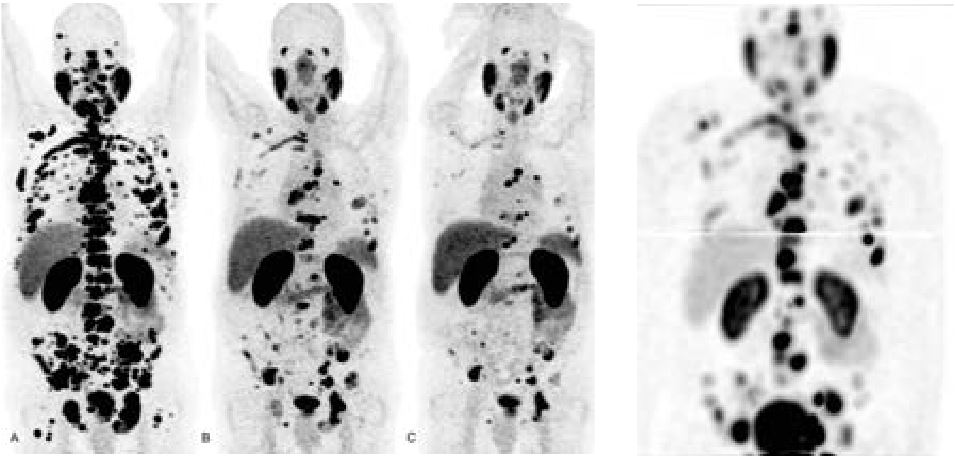

• Oncologie (métastases, tumeurs primitives, réponse au traitement...)

Nous étudions les organes, sains ou malades, à l'aide de traceurs radioactifs repérables par gamma-caméra ou PET scanner ("PET-scan"). Pour résumer, on peut dire que là où l'imagerie médicale donne une image du "comment c'est fait", nous nous attachons plutôt à définir le "comment ça marche".